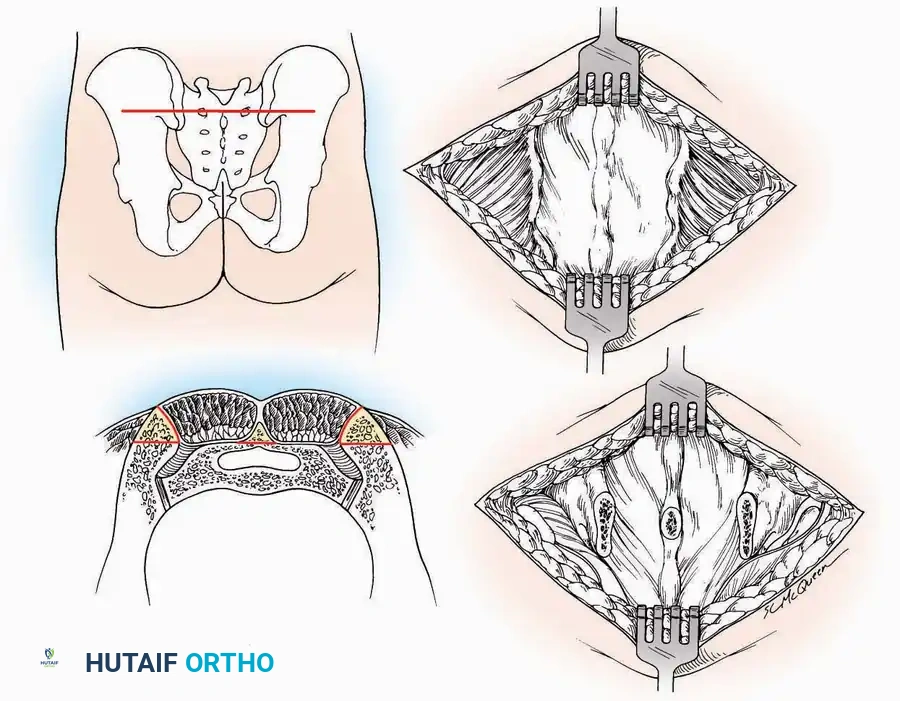

U Approach

Indications: Extensive plantar fasciotomy, radical tumor resection, or complex osteomyelitis debridement requiring access to the entire plantar surface of the calcaneus.

Positioning: Prone, with the leg supported on a large sandbag.

Surgical Technique:

* Incision: Join the medial and lateral approaches described above to form a large, continuous U-shaped incision around the posterior four-fifths of the calcaneus.

* Flap Elevation: Deepen the incision directly to bone. Elevate a massive plantar flap consisting of skin, the specialized fatty heel pad, and the plantar fascia. Retract this flap distally to expose the entire plantar calcaneal tuberosity.

Kocher Approach (Curved L)

Indications: Complete excision of the calcaneus (calcanectomy) for malignant tumors or recalcitrant osteomyelitis.

Surgical Technique:

* Incision: Incise the skin over the medial border of the Achilles tendon, starting 7.5 cm proximal to the calcaneal tuberosity. Extend it distally to the inferoposterior aspect of the tuberosity, curve it transversely around the posterior heel, and continue distally along the lateral surface of the foot to the tuberosity of the fifth metatarsal.

* Deep Dissection: Divide the Achilles tendon directly at its insertion and carry the dissection down to the bone.

* Enucleation: To reach the superior surface, free all tissues beneath the severed Achilles tendon. The calcaneus can then be enucleated subperiosteally or extraperiosteally depending on the oncologic or infectious margins required.